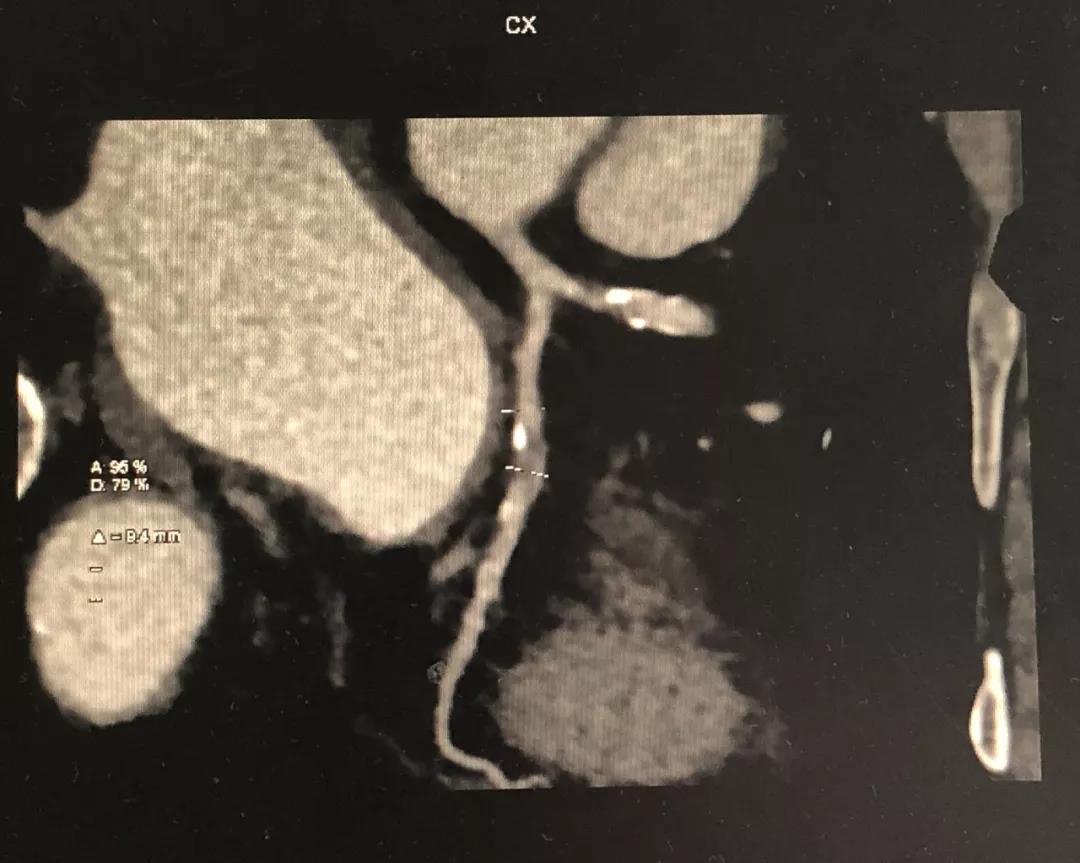

冠状动脉CTA

CCTA LAD病变特点:

中远段血管偏细

中远段血管病变弥漫

病变血管段有局灶点状钙化

CCTA LCX病变特点:

中段病变伴局灶点状钙化

1、明确了LAD病变位于血管的中远段,比较弥漫,病变段血管整体偏细,是应用药物球囊的适应症;

2、根据CCTA检查的结果,知晓病变的情况,预先准备好相应型号的药物洗脱球囊;

3、病变段血管为局灶性钙化,提示病变的预处理应该会很顺利;

4、病变近段的血管较直,相对健康,药物球囊入路通畅;